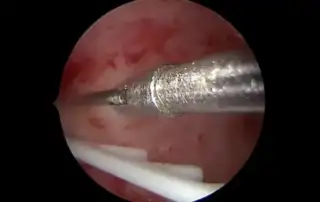

Pepper Training model for hysteroscopy ans sonographic image of adeno-myosis.

- The Integrated Animal Tissue – Bell Pepper Model A Cost-effective Haptic Training Model for Resectoscopic Surgery

Sanket Pisat, Pratik Sudhir Naik, Suchita Sanket Pisat, Saski Dilip Kadu

The Integrated Animal Tissue – Bell Pepper Model: A Cost-effective Haptic Training Model for Resectoscopic Surgery

DOI: 10.36205/trocar6.2025015